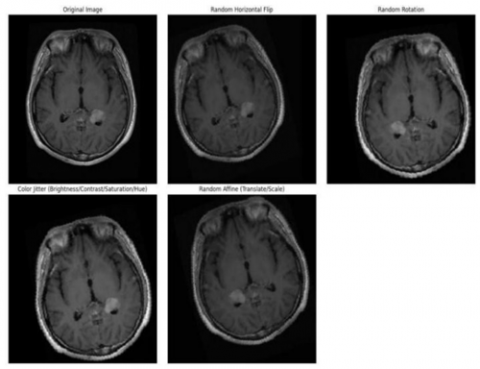

The following report details the complete approach of the proposed brain tumor classification system. The publicly accessible database provided brain MRI scan images, which are used for classification (Figure 2). A set of preprocessing operations is applied to establish consistency while increasing the input quality level. Process interventions start with a 224×224 pixels image resize, during which images become grayscale before receiving pixel normalization to stabilize the training process. Examples of augmented MRI images are provided in Figure 3. Data augmentation techniques that apply random rotation and horizontal flipping and scaling help enlarge dataset size while improving model generality. Image preprocessing completes before deep learning model application with the deployment of ResNet-18 architecture. The model operates with grayscale MRI data focusing on glioma and meningioma and pituitary tumor and no tumor classifications for training purposes. This phase instructs the model to detect patterned visuals that correspond to tumor classification, while validation tracks multiple epoch performance developments. The federated learning framework allows the development of an entire system to facilitate secure model training between simulated client nodes.

Figure 3. Sample of augmented images

The MRI images were preprocessed by converting grayscale scans into three channels and resized to 224×224 pixels. Data augmentation included random cropping, flipping (p = 0.5), rotation (±15°), color jitter, and sharpness adjustment to enhance variability. Finally, images were converted to tensors and normalized using ImageNet mean [0.485, 0.456, 0.406] and std [0.229, 0.224, 0.225].